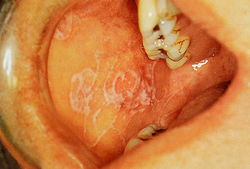

Красный плоский лишай встречается у 0,5-1,5% взрослого населения и проявляется как болезненные красные изъязвленные дефекты (эрозивные или буллезные) или как бессимптомные неэрозивные формы на слизистой оболочки щек, нёба, десен или языка. Неэрозивные дефекты включают белые стрии (полоски Уикхэма) и сетчатые структуры (рис. 23.5). Могут наблюдаться дефекты кожи.

Рис. 23.5 Ретикулярный или неэрозивный красный плоский лишай на слизистой щеки. Светлый сетевидный дефект. Этот тип лишая, по-видимому, протекает бессимптомно, в отличие от язвенных форм болезни (предоставлено John Wright).